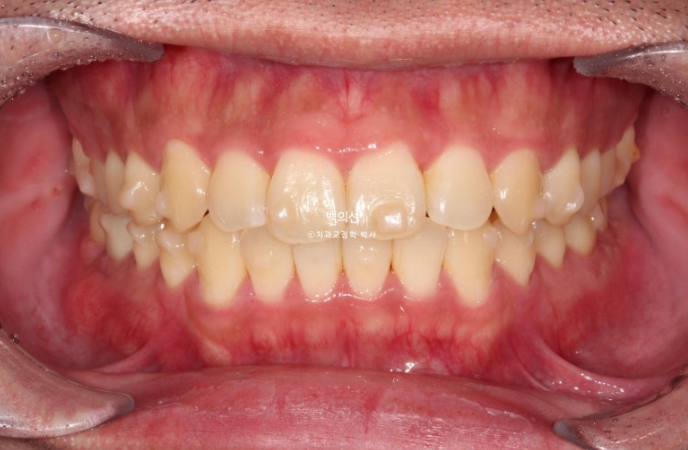

작년 1월, 교정치료를 위해 내원한 20대 환자분입니다. 동생과 같이 오셨는데 두 형제가 모두 훈훈한 외모에 성격도 좋고 매너도 좋은 그런 분들이었습니다.

앞니가 삐뚤하고 소위 나비치아 입니다. 맨 뒤 큰어금니가 바깥으로 덧니처럼 뻗쳐있습니다.

교합면 사진에서 나비치아와 바깥으로 나가있는 두번째 큰어금니가 잘 보입니다.

파란 화살표 치아끼리 엇갈려 물리는 가위교합으로 교합이 안되는 상태입니다.